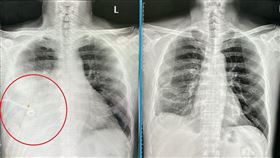

肺部「毛玻璃」影像嚇壞 醫:不等於癌症

隨著低劑量電腦斷層掃描(LDCT)被廣泛納入健檢項目...